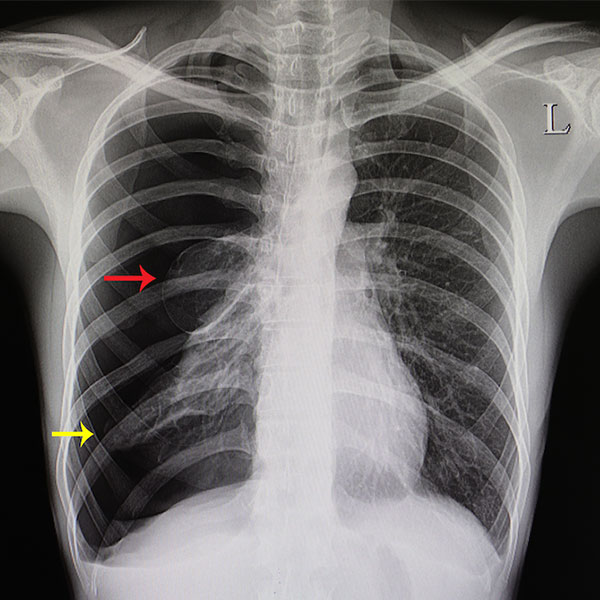

Pleural Effusion

Pleural effusion is fluid buildup between lung and chest wall, causing breathlessness, chest pain, and discomfort.

Pneumothorax

Pneumothorax is a collapsed lung caused by air leaking into the chest cavity, leading to breathing difficulty.